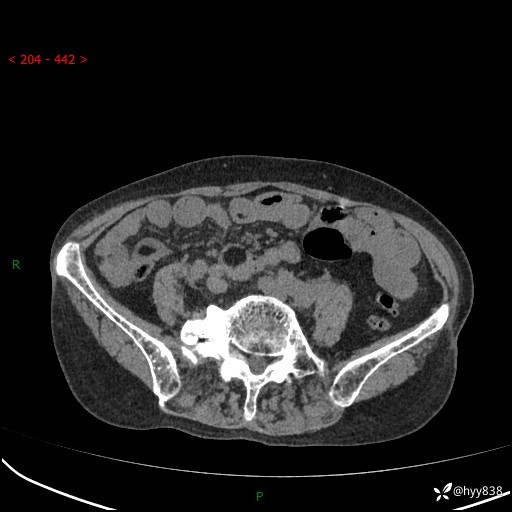

全腹部CT平扫